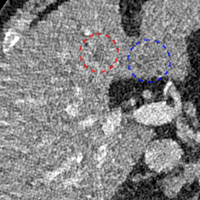

To show the denoising effect of the selected networks, we took two representative slices as shown in Figs. 5 and 7. And Figs. 6 and 8 are the zoomed regions-of-interest (ROIs) marked by the red rectangles in Figs. 5 and 7. All the networks demonstrated certain denoising capabilities. However, CNN-MSE blurred the images and introduced waxy artifacts as expected, which are easily observed in the zoomed ROIs in Figs. 6e and 8e. WGAN-MSE was able to improve the result of CNN-MSE by avoiding over-smooth but minor streak artifacts can still be observed especially compared to CNN-VGG and WGAN-VGG. Meanwhile, using WGAN or GAN alone generated stronger noise (Figs. 6g and 8g) than the other networks enhanced a few white structures in the WGAN/GAN generated images, which are originated from the low dose streak artifact in LDCT images, while on the contrary the CNN-VGG and WGAN-VGG images are visually more similar to the NDCT images. This is because the VGG loss used in CNN-VGG and WGAN-VGG is computed in a feature space that is trained previously on a very large natural image dataset [48]. By using VGG loss, we transferred the knowledge of human perception that is embedded in VGG network to CT image quality evaluation. The performance of using WGAN or GAN alone is not acceptable because it only maps the data distribution from LDCT to NDCT but does not guarantee the image content correspondence. As for the lesion detection in these two slices, all the networks enhance the lesion visibility compared to the original noisy low dose FBP images as noise is reduced by the different approaches.

As for iterative reconstruction technique, the reconstruction results depend greatly on the choices of the regularization parameters. The implemented dictionary learning reconstruction (DictRecon) result gave the most aggressive noise reduction effect compared to the network outputs as a result of strong regularization. However, it over-smoothed some fine structures. For example, in Fig. 8, the vessel pointed by the green arrow was smeared out while it is easily identifiable in NDCT as well as WGAN-VGG images. Yet, as an iterative reconstruction method, DictRecon has its advantage over post-processing method. As pointed by the red arrow in Fig 8, there is a bright spot which can be seen in DictRecon and NDCT images, but is not observable in LDCT and network processed images. Since the WGAN-VGG image is generated from LDCT image, in which this bright spot is not easily observed, it is reasonable that we do not see the bright spot in the images processed by neural networks. In other words, we do not want the network to generate structure that does not exist in the original images. In short, the proposed WGAN-VGG network is a post-processing method and information that is lost during the FBP reconstruction cannot easily be recovered, which is one limitation for all the post-processing methods. On the other hand, as an iterative reconstruction method, DictRecon algorithm generates images from raw data, which has more information than the post-processing methods.